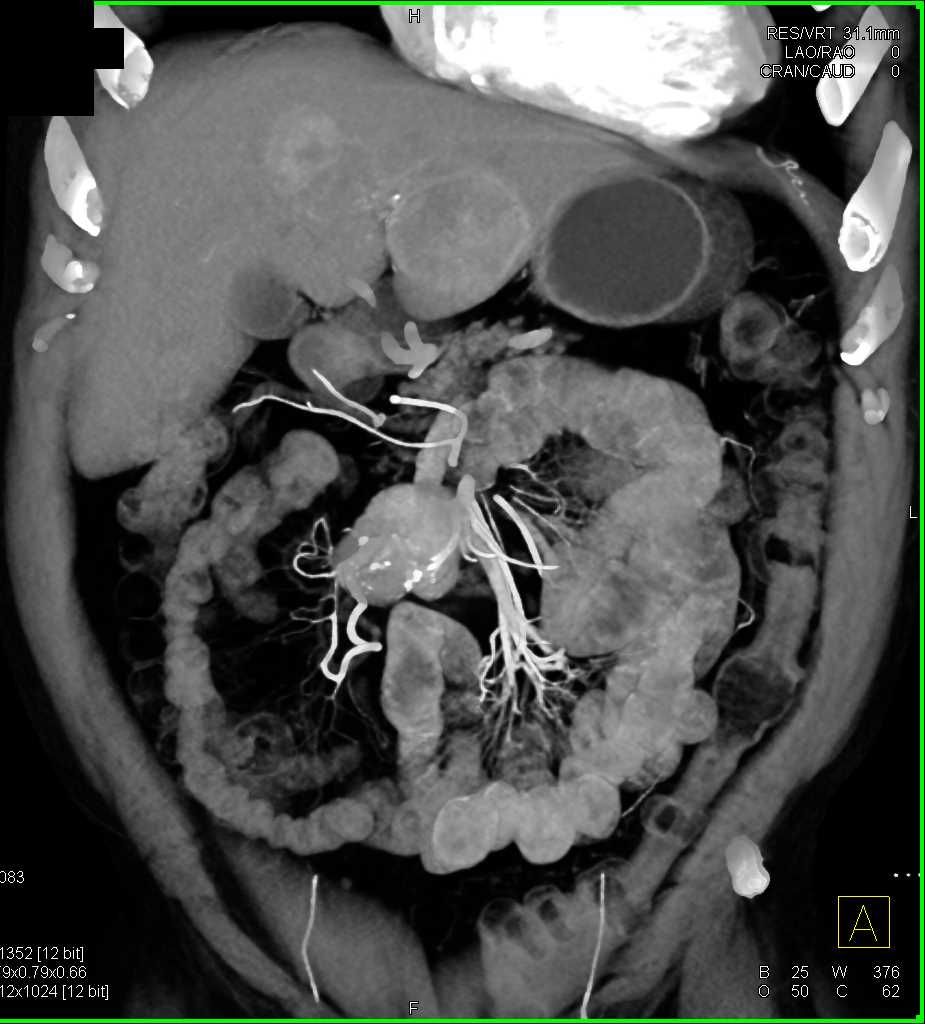

Carcinoid Tumor with Desmoplastic Reaction